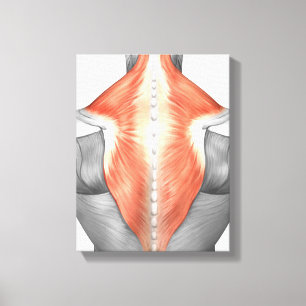

Impressão Em Tela Músculos da parte traseira e do pescoço

PreçoR$ 467,00

Produto oficialmente licenciado